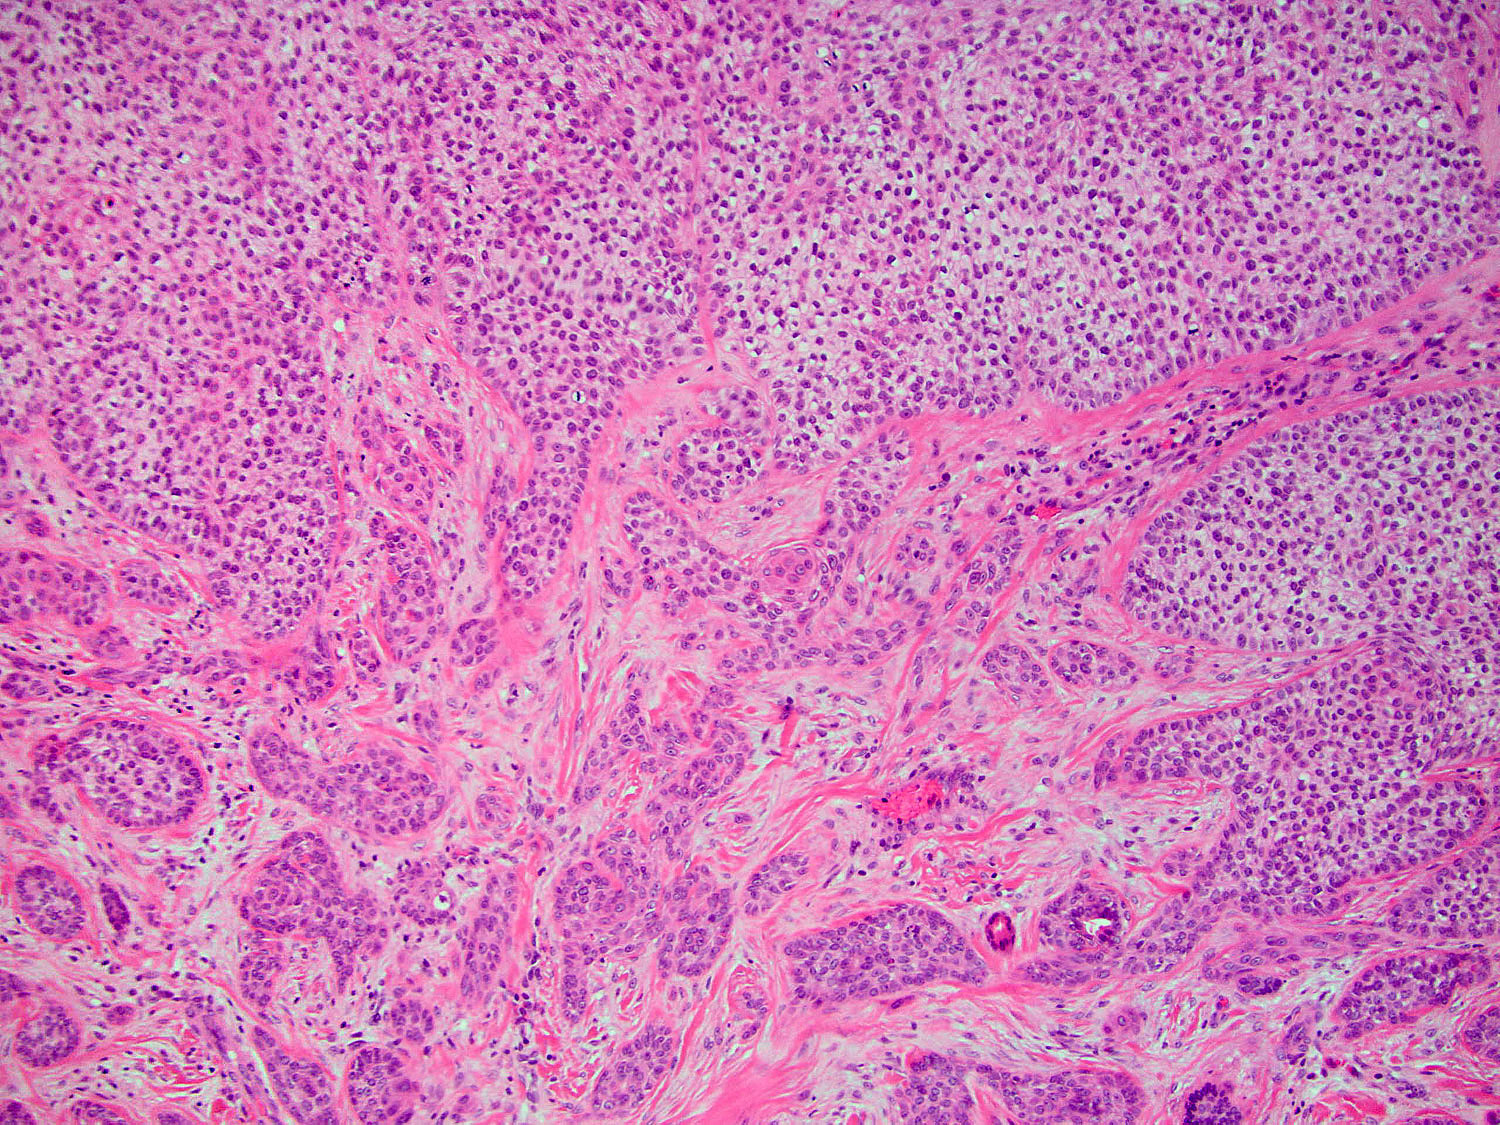

H&E staining (10x objective)